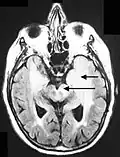

Imagen de RM en secuencia FLAIR que demuestra infiltración relacionada con tumor que involucra núcleos lenticulares (Flecha). -